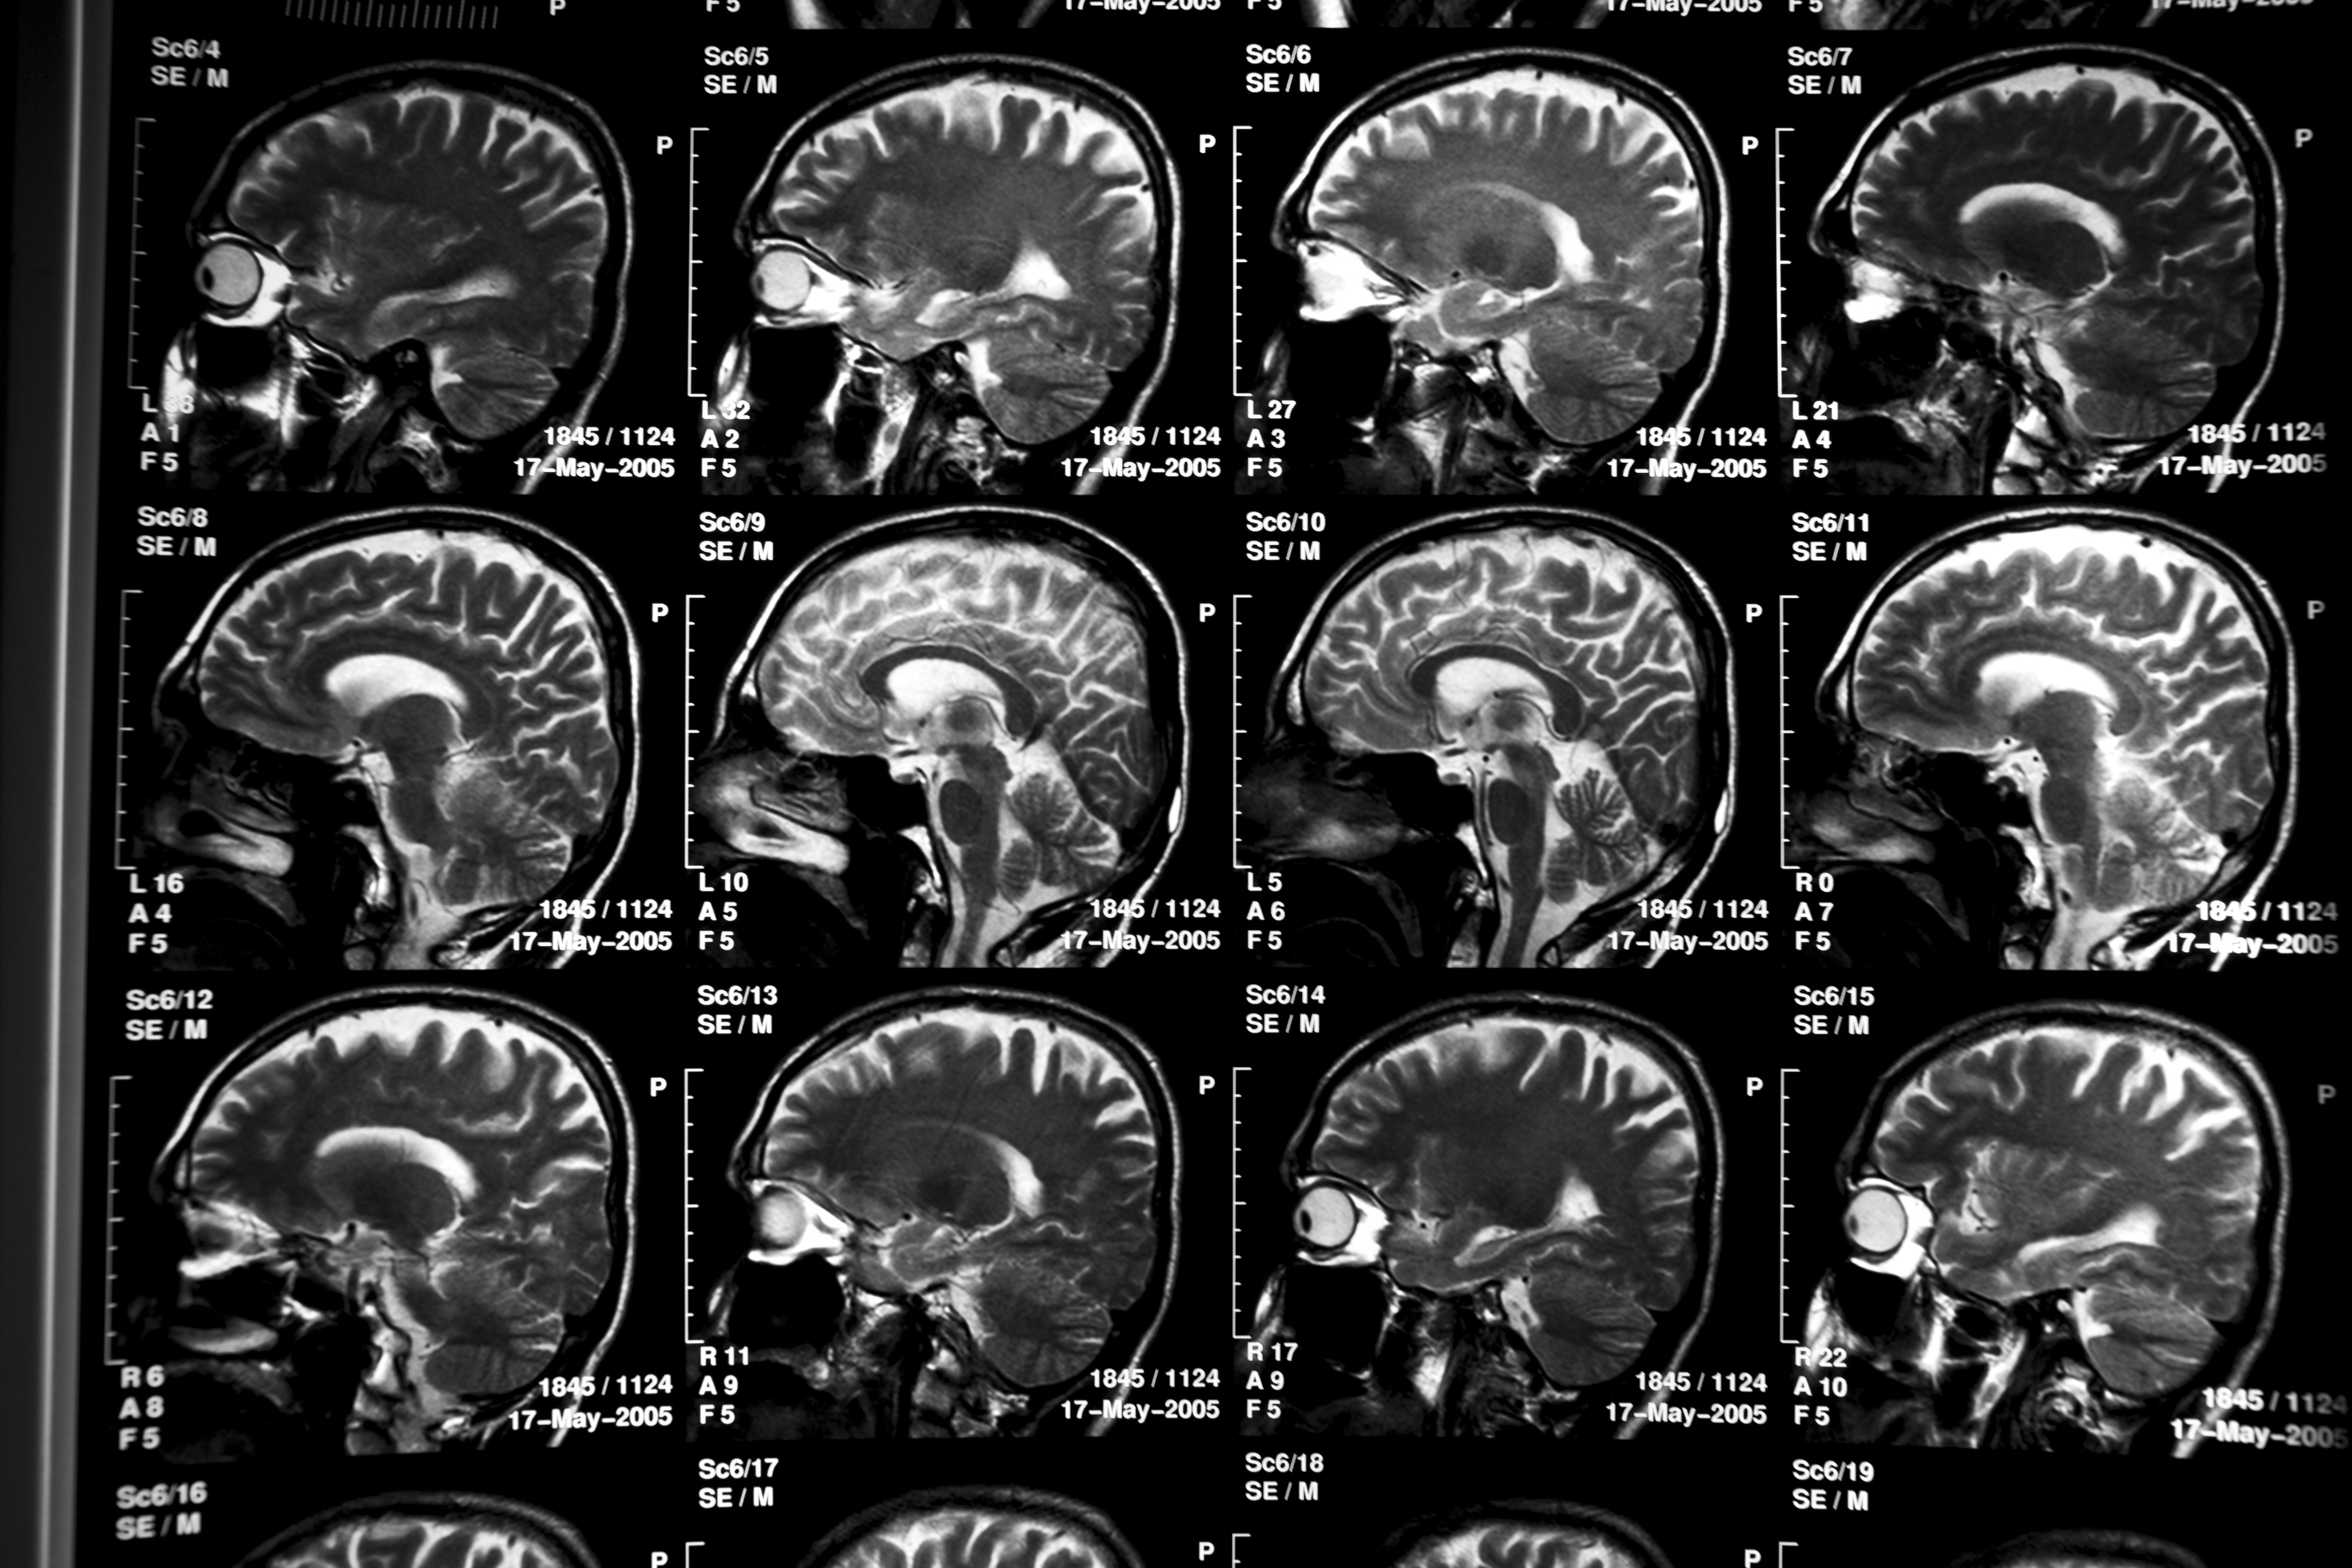

Cientistas da Universidade da Califórnia em San Diego (UC San Diego), nos Estados Unidos, identificaram pistas do porquê de alguns pacientes com Alzheimer continuarem lúcidos apesar de apresentarem as alterações cerebrais típicas da doença, como os acumulados de proteína beta-amiloide e tau. Entender melhor o quadro, conhecido como Alzheimer assintomático, pode abrir caminho para novos tratamentos, esperam os pesquisadores.

No novo estudo, publicado nesta semana na revista científica Acta Neuropathologica Communications, a equipe analisou a expressão gênica em milhares de amostras do cérebro humano e identificou padrões moleculares ligados à progressão ou à proteção contra a doença. De forma resumida, eles encontraram padrões genéticos ligados à ausência de sintomas em cérebros com alterações associadas ao Alzheimer.

Conduzido por pesquisadores do Centro para Envelhecimento Cerebral Saudável da Universidade de Nova Gales do Sul, na Austrália, o estudo mostra que os avanços da neuroimagem moderna e da análise de biomarcadores no líquido cefalorraquidiano, fluido que circula entre o cérebro e a medula espinhal, têm possibilitado novas compreensões sobre a resiliência do órgão.

Os pesquisadores afirmam que, ao integrar testes cognitivos com exames de imagem e biomarcadores de fluidos, será possível identificar melhor quem é resiliente, por que apresenta essa resiliência e como intervenções podem ajudar a preservar a cognição mesmo quando há doença cerebral presente.